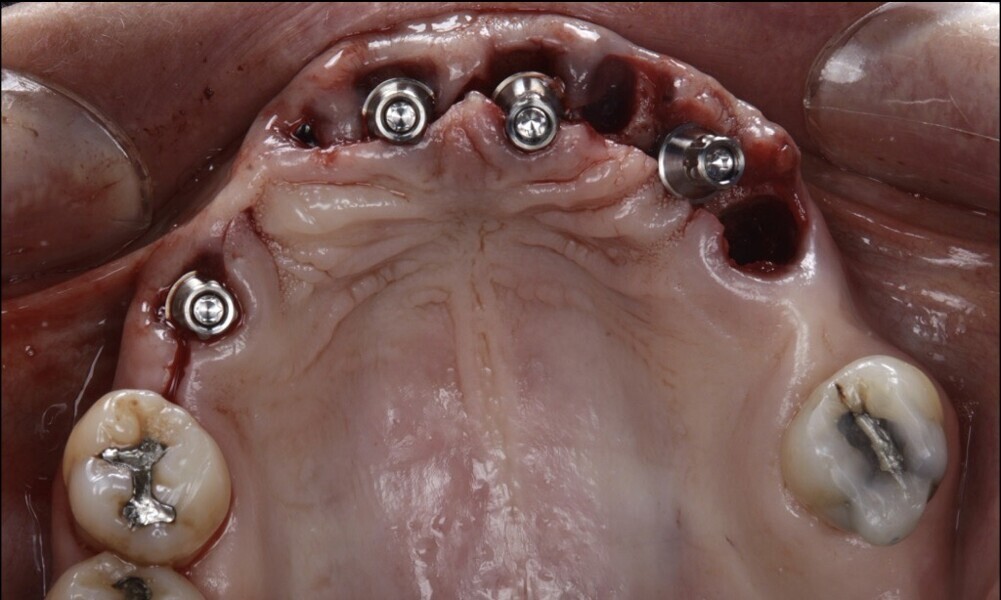

After treating the mandibular arch, we proceeded with the maxillary arch. The flap design involved a flapless approach for the maxillary arch. All teeth in the maxillary arch were extracted, except for the molars (Figs. 51 & 52). The provisional restoration was seated and adapted to the mouth after the tooth extractions (Figs. 53–55). The implant sites were prepared following the manufacturer’s instructions, the implants were subsequently inserted and screw-retained abutments (Straumann) were placed (Figs. 56 & 57). Guided bone regeneration with Straumann XenoGraft and a resorbable membrane (Straumann) were then performed (Figs. 58–60).

Figs. 56–60: The implants were placed, guided bone regeneration was performed using a xenograft and screw-retained abutments were placed.